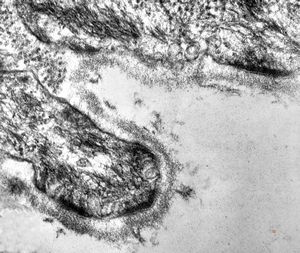

M, 3y. | cutaneous nerve